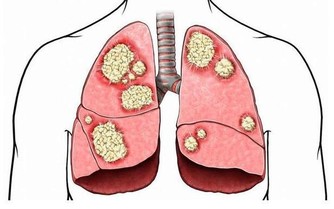

有時需要換肝這種高難度的手術,手術過程複雜多樣,

在做這種手術時,對於病人來說需要開胸,自己衣服上可能攜帶一些病菌,在手術過程中造成不必要的影響,